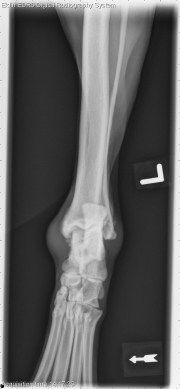

Today’s case is a 7-year-old male neutered Labrador retriever. Owner noticed a lump on his left hock about 5 days ago. What are your findings?

There is a thin, radiolucent fracture line present in an oblique orientation on the proximal talus. This is best seen on the caudocranial projection. There is new bone proliferation on the medial and lateral aspects of the talus near the fracture margin. There is increased soft tissue opacity at the level of the tarsocrural joint indicating effusion. On stressed projections, the medial tibiotarsal joint is slightly widened. The arrows indicate the direction of stress applied to the joint.

Note – was not a true fracture.

Chronic, non displaced fracture of the left talus with marked tarsocrural effusion and osteoarthrosis. Mild joint instability may indicate disruption of the medial collateral ligaments.